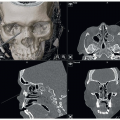

High-resolution (slices of 1 mm or less) 3D CT scan is essential to evaluate the size and thickness of the skull defect as well as for computer design of the reconstructive implant (FIG 1).

A full-thickness skull defect is obvious on physical exam and by 3D CT scan.